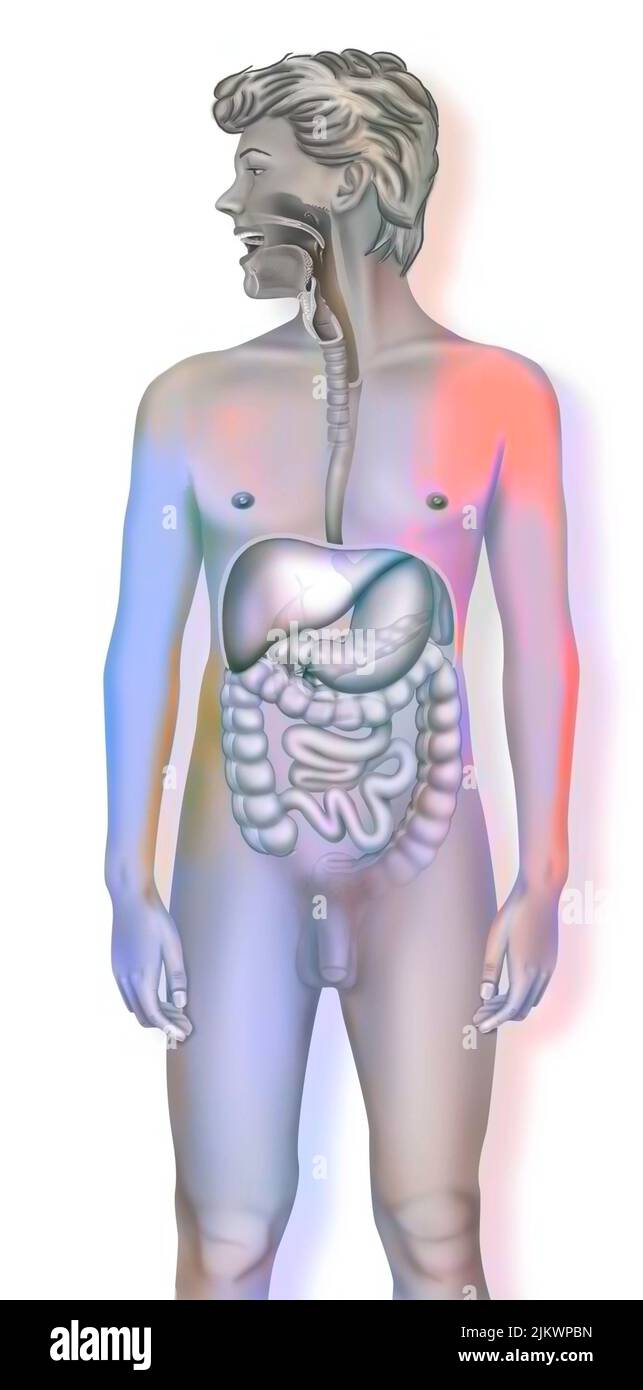

RFPAYTH0–Innere Organe, männlichen Körper - schematische Darstellung der menschlichen Anatomie Illustration - auf weißem Hintergrund.